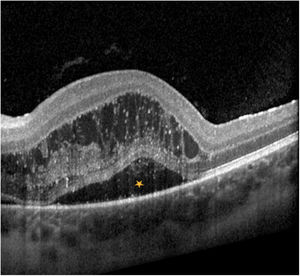

Presentamos un paciente de 13 años con fiebre, disminución de la visión y alteración en la discriminación de los colores unilateral. La analítica y la TC craneal fueron normales. En el fondo de ojo presentaba edema de papila con edema de la retina peripapilar (fig. 1) y en la tomografía de coherencia óptica (OCT) se constató edema macular (fig. 2), compatible con neurorretinitis. El diagnóstico fue serológico (positivo para Bartonella henselae).

La neurorretinitis por B. henselae es un diagnóstico infrecuente. La pérdida de agudeza visual unilateral con edema de papila y exudación macular (estrella macular) en la funduscopia es característica1–3. La estrella macular suele observarse 1-4 semanas desde el inicio y persiste meses (fig. 3)2. El tratamiento consiste en biterapia antibiótica (doxiciclina y rifampicina) de larga duración. El tratamiento corticoideo es controvertido, aunque parece mejorar el pronóstico de la agudeza visual y las alteraciones funduscópicas1,3.